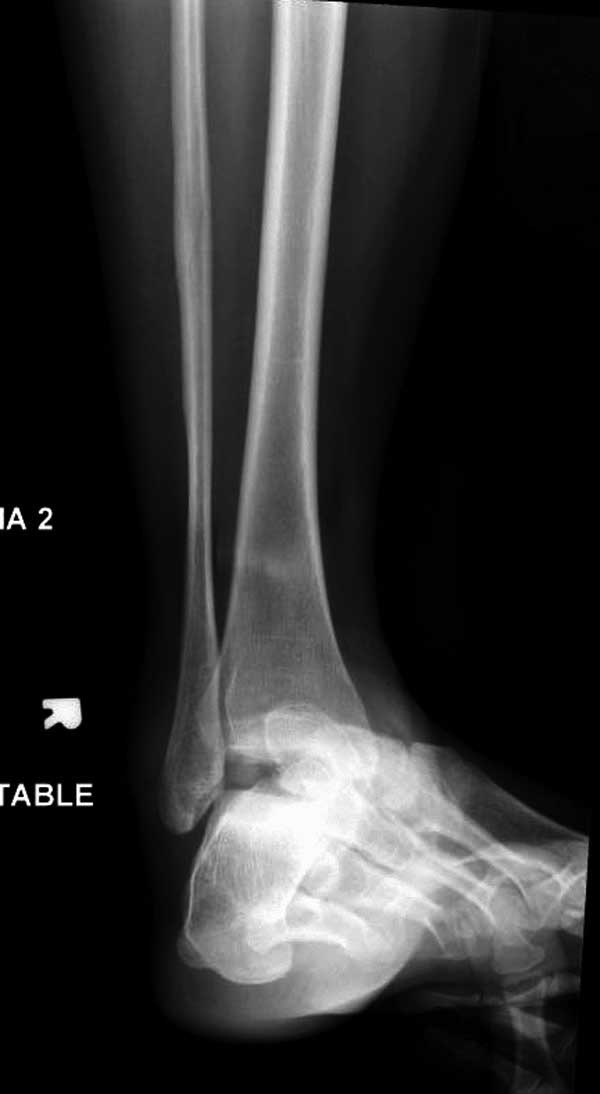

3) Переломовывих таранной кости: фиксация в спицевом или спицестержневом АНФ (1-2 стержня или 2 спицы ср/3 диафиза б/б кости, 2 спицы дистальный конец б/б кости, 3-4 спицы пяточная кость, 1 спица плюсневые кости), дистракция и репозиция в аппарате.

Учитывая тяжесть травмы, пациентка скорее всего попадает под DCO. Ночью стабилизировать бедро стержневым аппаратом, вывих попробовать вправить, зафиксировать гипсом или аппаратом (в зависимости от состояния кожных покровов. Таз стабилизировать простынею. Перевод в реанимацию. По стабилизации, состояния: открытое вправление, внутренняя фиксация перелома головки, тарана, АВФ на таз, штифтование бедра (последнее - можно еще отложить)

вправление вывиха - имелось ввиду переломовывих тарана.

Больная стабильная после хирургических мероприятии и получив добро, приступили к закрытому вправлению таранной кости с укладкой наружного фиксатора. Затем укладка больную на бок и открытый остеосинтез перелома-вывиха головки бедра.

После спадения отека на стопе произведена фиксация тарана. Кстати, коллеги пересмотрели первоначальную консультацию по позвоночнику и на двух уровнях провели фиксацию. Из-за длительного постельного режима без нагрузки таз не стали оперировать...